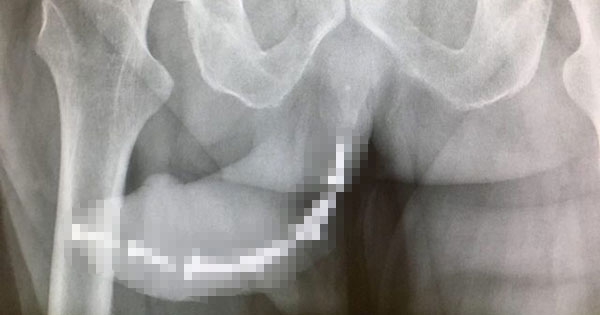

生病接受治疗时,患者很担心遇到庸医。马其顿斯科普里女子Jasminka Velkovska就遇到了这样的事。3年前她被检查出结肠癌,去医院做肿瘤切除手术,没想到手术完毕后癌症没治…